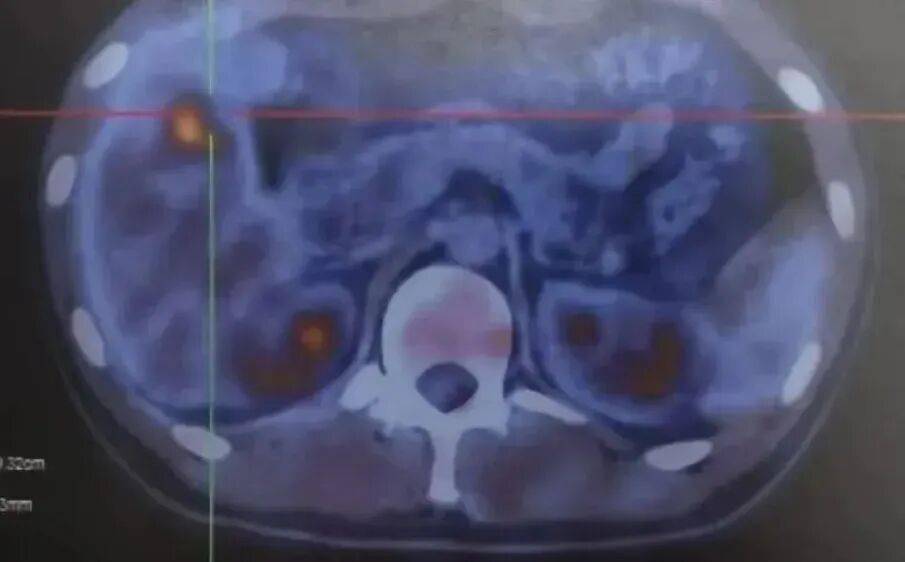

亚甲炎,作为一种常见却常被忽视的甲状腺病症,往往令患者历经多番周折方才确诊。该病症的症状复杂多变,常被误认为是“上呼吸道感染”、“咽炎”、“急性扁桃体炎”或是“甲状腺功能亢进症”,这无疑增加了误诊和漏诊的风险。

亚甲炎发病迅速,患者常出现食欲减退、肌肉酸痛、发热、心率加快、多汗等全身性不适。然而,最具特征性的症状仍是甲状腺部位的疼痛,此类疼痛往往可扩散至耳部、下颌或颈后,尤其在吞咽时疼痛感会加剧。甲状腺腺体会出现肿胀和硬化,部分患者还会伴随颈部淋巴结的肿大。